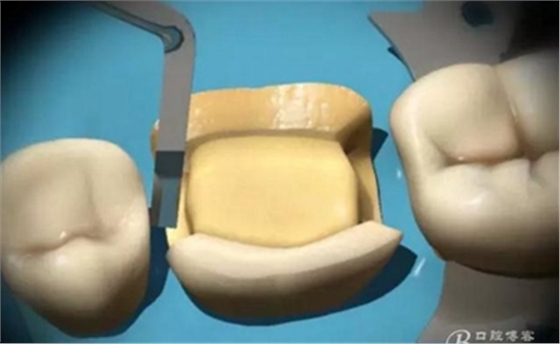

制作完成

高嵌體

試戴